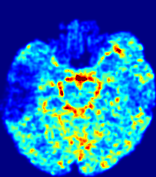

LesionRefer to captionRefer to captionRefer to captionRefer to captionRefer to captionRefer to caption𝐕rgbsubscript𝐕𝑟𝑔𝑏{\bf{V}}_{rgb}Refer to captionRefer to captionRefer to captionRefer to captionRefer to captionRefer to caption𝐕2subscriptnorm𝐕2{\|\bf{V}}\|_{2}Refer to captionRefer to captionRefer to captionRefer to captionRefer to captionRefer to captionRefer to caption3.53.53.52.82.82.82.12.12.11.41.41.40.70.70.70.00.00.0(mm/s)𝑚𝑚𝑠(mm/s)D𝐷DRefer to captionRefer to captionRefer to captionRefer to captionRefer to captionRefer to captionRefer to caption0.0200.0200.0200.0160.0160.0160.0120.0120.0120.0080.0080.0080.0040.0040.0040.0000.0000.000(mm2/s)𝑚superscript𝑚2𝑠(mm^{2}/s)Slice #1Slice #2Slice #3Slice #4Slice #5Slice #6

Figure 3: PIANO feature maps for one stroke patient, where the lesion is located in the left hemisphere. Top row: segmented stroke lesion region (white) on different slices, obtained from ISLES 2017. The corresponding slices for the PIANO feature maps are shown in the following rows.

For a better insight into an estimated velocity field 𝐕𝐕{\bf{V}} and diffusion field 𝐃𝐃{\bf{D}}, we compute the following maps: (1) 𝐕rgbsubscript𝐕𝑟𝑔𝑏{\bf{V}}_{rgb}: Color-coded orientation map of 𝐕=(Vx,Vy,Vz)T𝐕superscriptsuperscript𝑉𝑥superscript𝑉𝑦superscript𝑉𝑧𝑇{\bf{V}}=(V^{x},V^{y},V^{z})^{T}, obtained by normalizing 𝐕𝐕{\bf{V}} to unit length and mapping its 3 components to red, green, blue respectively; (2) 𝐕2subscriptnorm𝐕2\|{\bf{V}}\|_{2}: 222 norm of 𝐕𝐕{\bf{V}}; (3) D𝐷D: scalar field in Eq. 5.

Fig. 3 and Fig. 4 show the PIANO feature maps estimated from two ISLES 2017 patients: all are highly consistent with the lesion in both cases. Details of the blood flow trajectories are revealed in 𝐕rgbsubscript𝐕𝑟𝑔𝑏{\bf{V}}_{rgb} by the ridged patterns and the sharp changes of colors in the unaffected (right) hemisphere, while the flat patterns appearing within the lesion provide little directional information about the velocity and indicate low velocity magnitudes. Velocity magnitudes are more directly visualized via 𝐕2subscriptnorm𝐕2\|{\bf{V}}\|_{2}, from which one can easily locate the lesion where 𝐕2subscriptnorm𝐕2\|{\bf{V}}\|_{2} is low. D𝐷D also indicates lower diffusion values in the lesion, though with less contrast potentially due to the fact that it captures the accumulated effect of CA diffusion at the voxel-level.